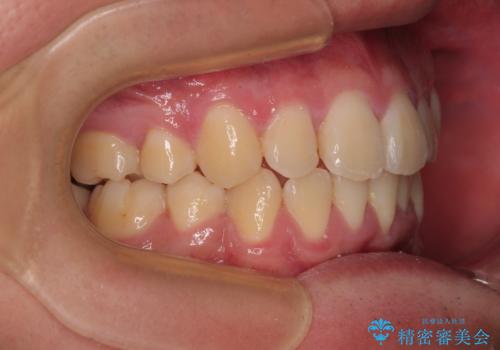

移動が順調に進み、1年半の短期間で治療を終えることができました。

前方に突出した上顎前歯の傾斜も改善されました。